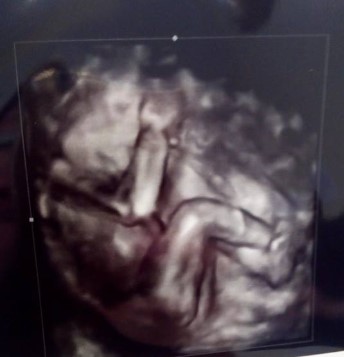

Reyna T. nos ha enviado la eco de su bebé. Ecografía de 28 semanas de gestación.

A las 28 semanas de gestación, el feto mide aproximadamente 37 centímetros y pesa alrededor de 1.000 gramos. Estos valores pueden variar, pero dan una idea general del tamaño del bebé. En esta fase, el crecimiento es rápido y constante.